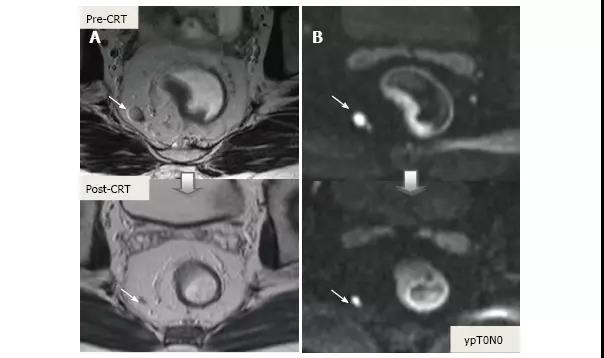

3.N 分期

CRT 后淋巴结大小用于重新分期更可靠,放疗导致的正常淋巴结形态学变化使得转移淋巴结与正常淋巴结很难采用形态学和 DWI 相区分,经常导致淋巴结过度分期(图 24 和图 25)。

图 24. DWI 对直肠癌放化疗后 ypT0N0 直肠系膜淋巴结评估假阳性。A. T2 加权轴位磁共振图像显示放化疗后结节大小明显减少,与阴性淋巴结(箭头)相符;B. DWI 图像,直肠周围淋巴结治疗后高弥散信号,与阳性淋巴结(箭头)相符。

图 25. DWI 成像,直肠癌放化疗后 ypT0N0 阳性直肠系膜淋巴结。A. T2 加权轴位图像显示淋巴结大小明显减少,与完全反应相符;B. 残余的纤维化淋巴结呈现高弥散信号强度,错误提示为转移性淋巴结(箭头)。

MRI 重新分期的精确性通常低于初始分期,主要源于淋巴结过度分期,不能区分肿瘤浸润、肿瘤残留、治疗反应与纤维化的差异。有 meta 分析显示新辅助治疗后 MRI 重新分期的精确性变化很大,但如果联合 DWI、有经验的专家结果会更好,也有报道 MRI 可用于 CRM 分期,但对淋巴结分期则一直是挑战。